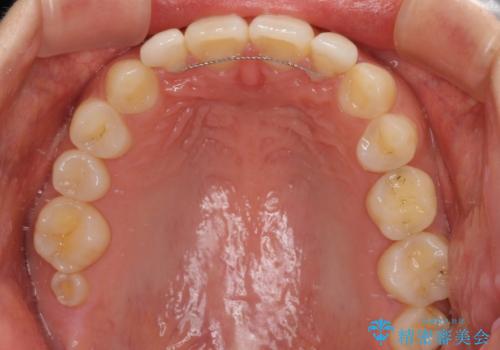

着色の原因として、湿気の多い環境で接着操作を行うと、境目に細かいギャップができてしまうことが考えられます。

接着の際にはラバーダムを使用して、乾燥した環境を整えて処置を行いました。